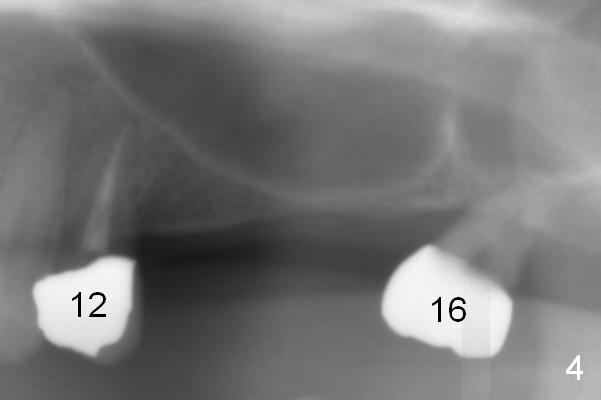

A 64-year-old man (MM) had caries at the tooth #12 (Fig.1), requiring root canal therapy (RCT, Fig.2). One year later, the periapical radiolucency reduces (Fig.3 <, as compared to that in Fig.2). The tooth remains asymptomatic 7 years posts RCT (Fig.4). A year later, the tooth has pain and buccal gingival swelling (probing tenderness); periradicular radiolucency is evident (Fig.5 arrowheads). It appears that the root fractures. Between the 7th and 8th years post RCT, the patient masticated mainly on the left side, while implants were placed at #30 and 31. The patient plans to have 4 implants in the upper left sextant (Fig.6). While implants are being placed at the site of #12 (Clindamycin) and 13, sinus lift seems mandatory at the sites of #13 and (initial depth will be 5-6 mm). By the time implants to be placed at #14 and #15, the bone height may increase.